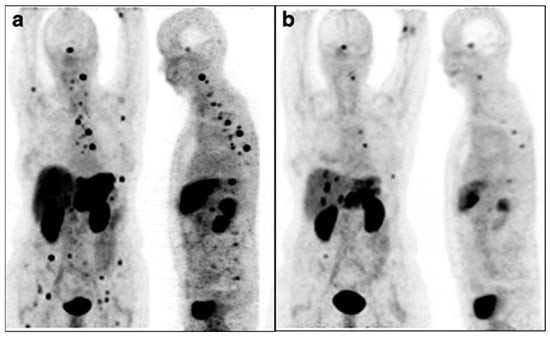

The strongest example supporting the use of a radioisotope with α-particle emissions delivered by an alternate route was from Kratochwil et al., who used Bi-213-DOTATOC-delivered IA to overcome previous resistance to Y-90-DOTATOC therapy [55]. Patients underwent an interventional procedure to deliver therapy to the hepatic artery, meaning the treatment went to most of the liver. Further, the leakage of therapy into the systemic system allowed for treatment of disseminated sites, which is shown in Figure 6. While this study did not compare IA to IV as closely as others, it represents a major advancement in understanding both α-particle therapy and IA delivery of radiopharmaceuticals.

Figure 6.

Intra-arterial Bi213-DOTATOC overcomes Y90-DOTATOC resistance. Ga-68-DOTATOC-PET imaging shows bulky liver disease and widespread lesions before treatment (a). Reduction in both primary liver and metastatic disease was seen on imaging six months after administration of Bi-213-DOTATOC into the common hepatic artery (b). This research was originally published in the European Journal for Nuclear Medicine and Molecular Imaging [55]. https://creativecommons.org/licenses/by/4.0/legalcode, accessed on 1 February 2023.